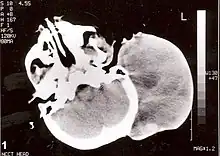

| Non-contrast CT scan of head showing a large mass without any intracranial extension. The diagnosis was post-auricular congenital alveolar rhabdomyosarcoma. | |

Following diagnosis and histopathological analysis, various imaging techniques may be used, including MRI, ultrasound, and a bone scan in order to determine the extent of local invasion and any metastasis. Further investigational techniques may be necessary depending on tumor sites. A parameningeal presentation of RMS will often require a lumbar puncture to rule out metastasis to the meninges. A paratesticular presentation will often require an abdominal CT to rule out local lymph node involvement, and so on. Outcomes are strongly tied to the extent of the disease, and its early mapping is important for treatment planning.